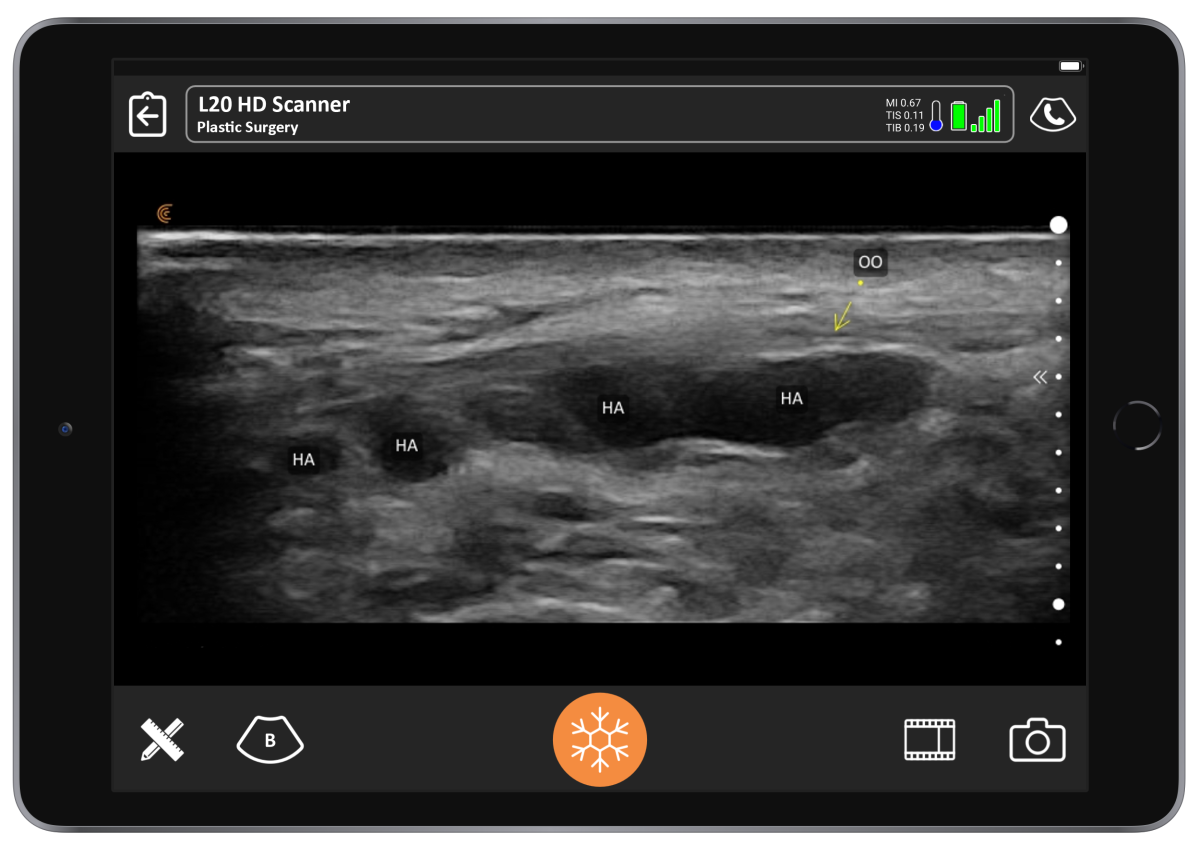

Figure 4 from Dynamic High‐Resolution Ultrasound In Vivo Imaging of Hyaluronic Acid Filler Face Filler Ultrasound Interest in doppler ultrasound (dus) analysis of the face has grown in cosmetic medicine, in particular for injectable fillers. In the context of filler application, live visualization with ultrasound can be utilized pre and postprocedurally to evaluate critical. The article reviews the types, properties,. Face Filler Ultrasound.